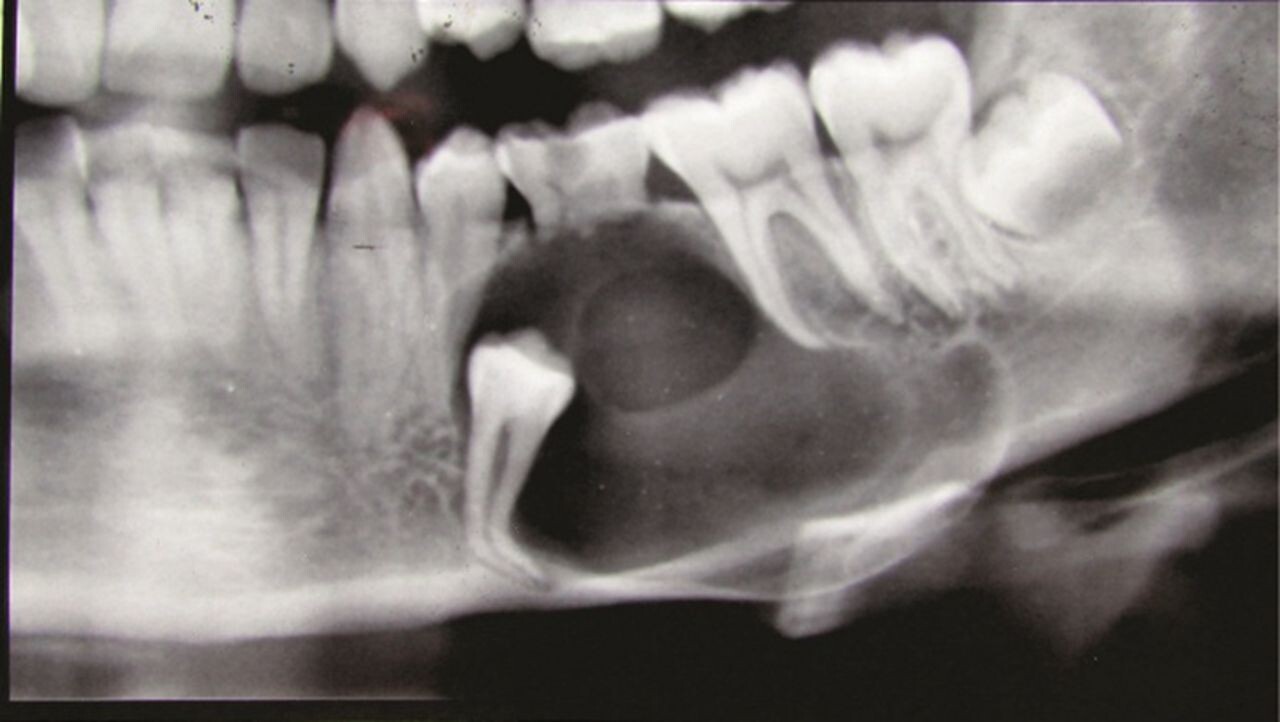

A dentigerous cyst is a smooth, round sack of clear fluid that slowly develops in the gums where an adult tooth is coming in. The Mayo Clinic says that they're the most common cyst to impact the jaw, and they're mostly found on the lower jaw (mandible) around wisdom teeth, but they can form around other teeth. They are generally painless and usually benign (not harmful); however, they can cause damage if they continue growing. According to the American Dental Association, cysts could harm "the roots of nearby teeth or destroy the bone that supports your teeth."

Because these cysts grow slowly and are often near the back of your mouth, you probably wouldn't even know one is there until your dentist tells you about it. They could see it in a routine examination. If your dental professional is checking on your wisdom teeth coming in, they may use a radiograph (x-ray) and discover it, or an orthodontist may notice a dentigerous cyst during a consultation for braces or clear aligners.

These growths can get big enough that you would feel it, but that is rare. If you have a larger cyst, it could impact the teeth on either side of the growth, adversely affecting the roots of those teeth and potentially even moving those teeth out of position.